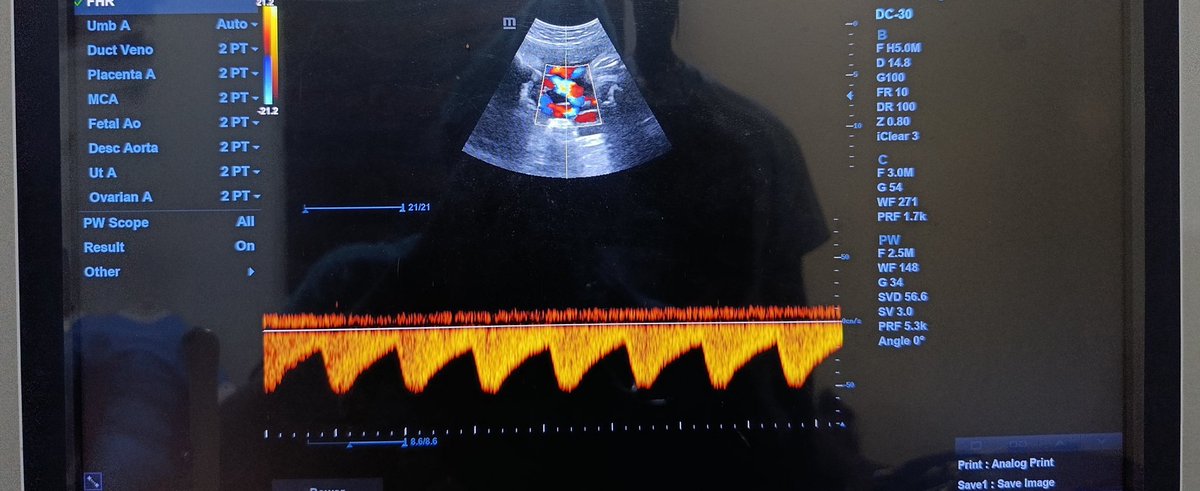

@popoolaadaniel First image: reversed end diastolic flow: ?iugr second: absent end diastolic flow: ? Placental insufficiency or issues Third image: normal sharp systolic forward flow followed by normal end diastolic flow just inverted